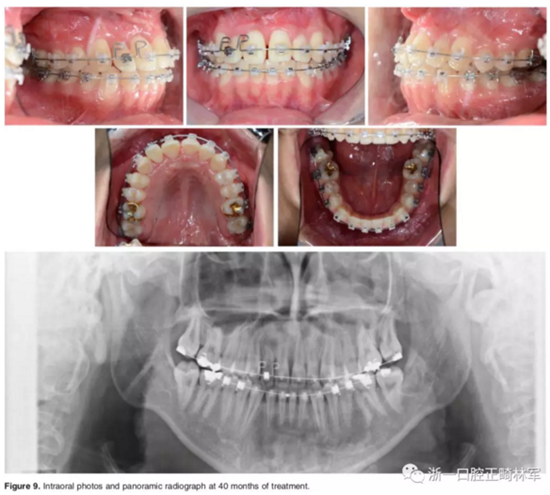

結(jié)束階段:

治療40個(gè)月后,3顆阻生牙位置已靠攏,繼續(xù)進(jìn)行排齊。使用高轉(zhuǎn)矩托槽及帶L型曲的0.019*0.025-inch Beta鈦絲對(duì)側(cè)切牙進(jìn)行轉(zhuǎn)矩控制,再在雙頜使用0.019*0.025-inch不銹鋼絲進(jìn)行排齊。矯治結(jié)束后,去除托槽、弓絲,雙頜前牙區(qū)粘接保持器。

影像學(xué):頭顱側(cè)位片示:矢狀向和垂直向骨骼發(fā)生變化(ANB角,3°;SN-MP,51°);上頜切牙略前傾(U1-SN,106°),與下頜切牙一致(IMPA,75°);病人的面部輪廓得以保持。全景片示:由于牙齒萌出,上前牙區(qū)垂直向牙槽骨水平增加;雖然前牙牙根較彎曲,但其平行度仍可,且無(wú)明顯的牙根吸收。CBCT示:前牙唇側(cè)骨質(zhì)連續(xù)性改善,牙根唇側(cè)支持組織變好,牙槽骨高度、厚度均有增加,但轉(zhuǎn)矩的改變一定程度上導(dǎo)致了局部應(yīng)力的增大。